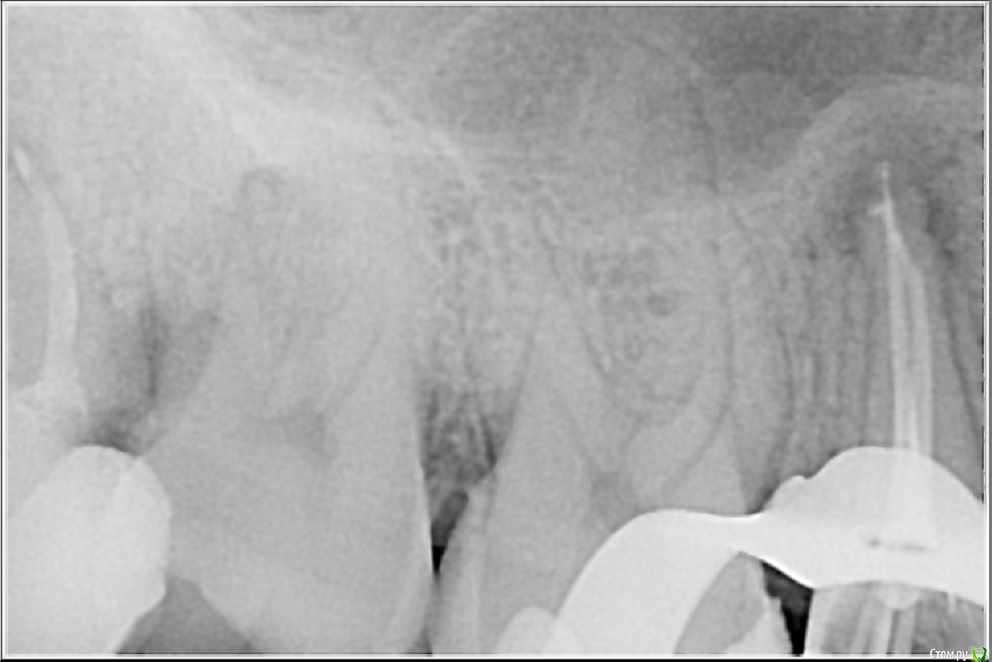

По закону парных случаев с интервалом в неделю приходит обострение хронического периодонтита 15 с каналонаполнителем в вестибулярном канале. Стандартная обработка. На обтурации долго возился с определением рабочей длинны и видимо получилось так себе... Аверон не тащит, да и снимок не всегда объективен. Коплю на Морита Root ZX Mini)))